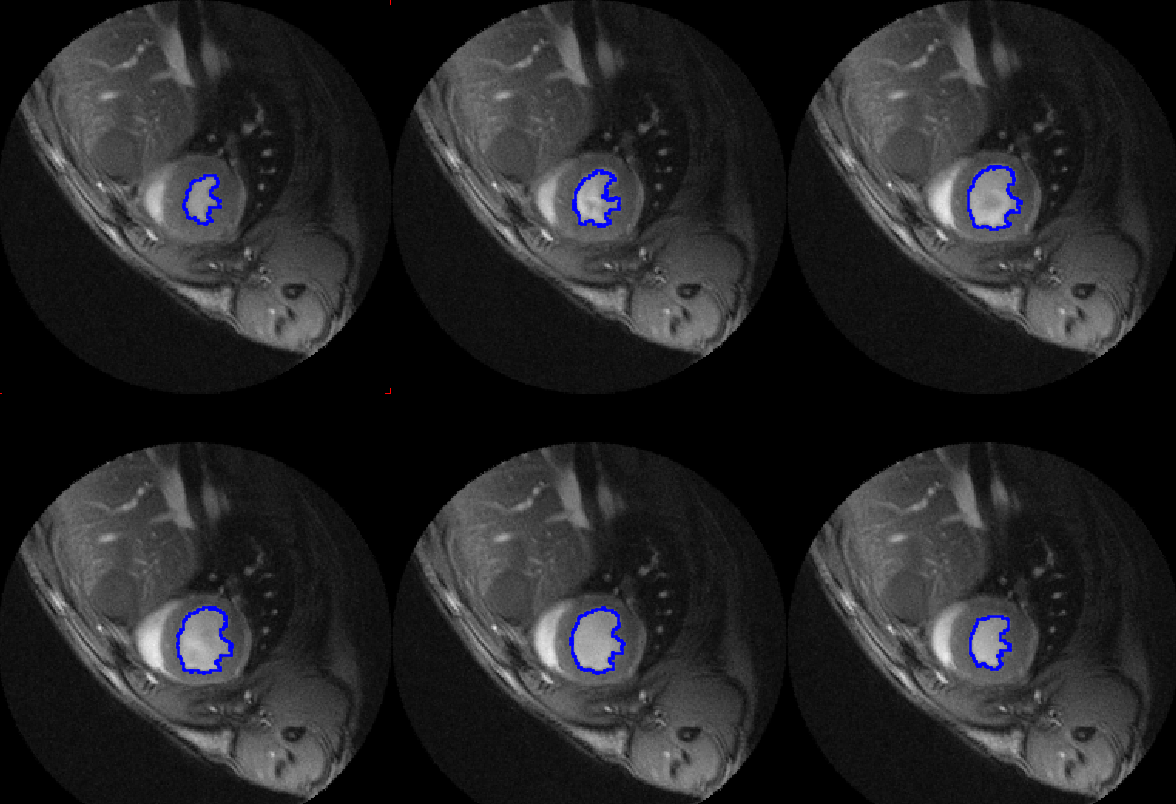

• Multimodality segmentation

• AI-based segmentation

• Ventricular function